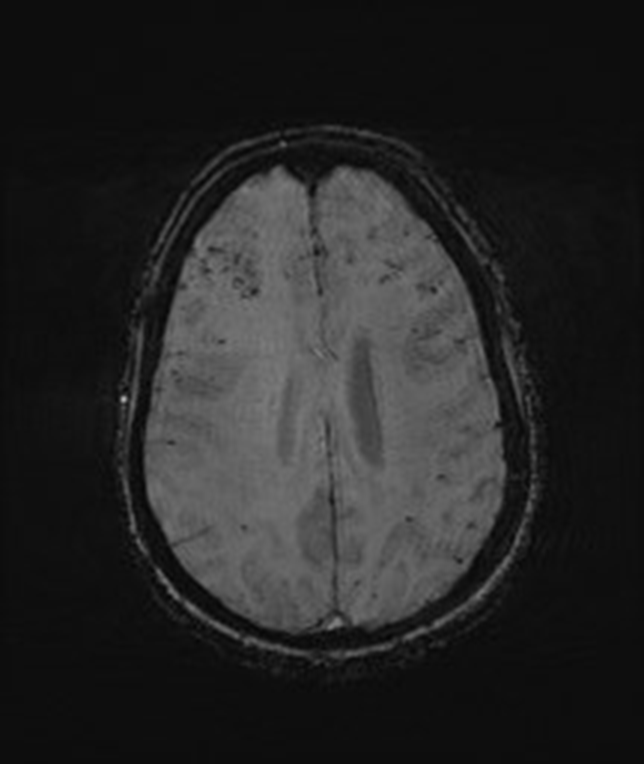

Useful MR modality for for identifying microhemorrhages 2/2 diffuse axonal injury (DAI) or amyloid angiopathy

susceptibility-weighted imaging (SWI)

amyloid angiopathy

MRI lesions oriented perpendicularly to the lateral ventricles seen in MS

Dawson's Fingers

Represents demyelination along periventricular venules